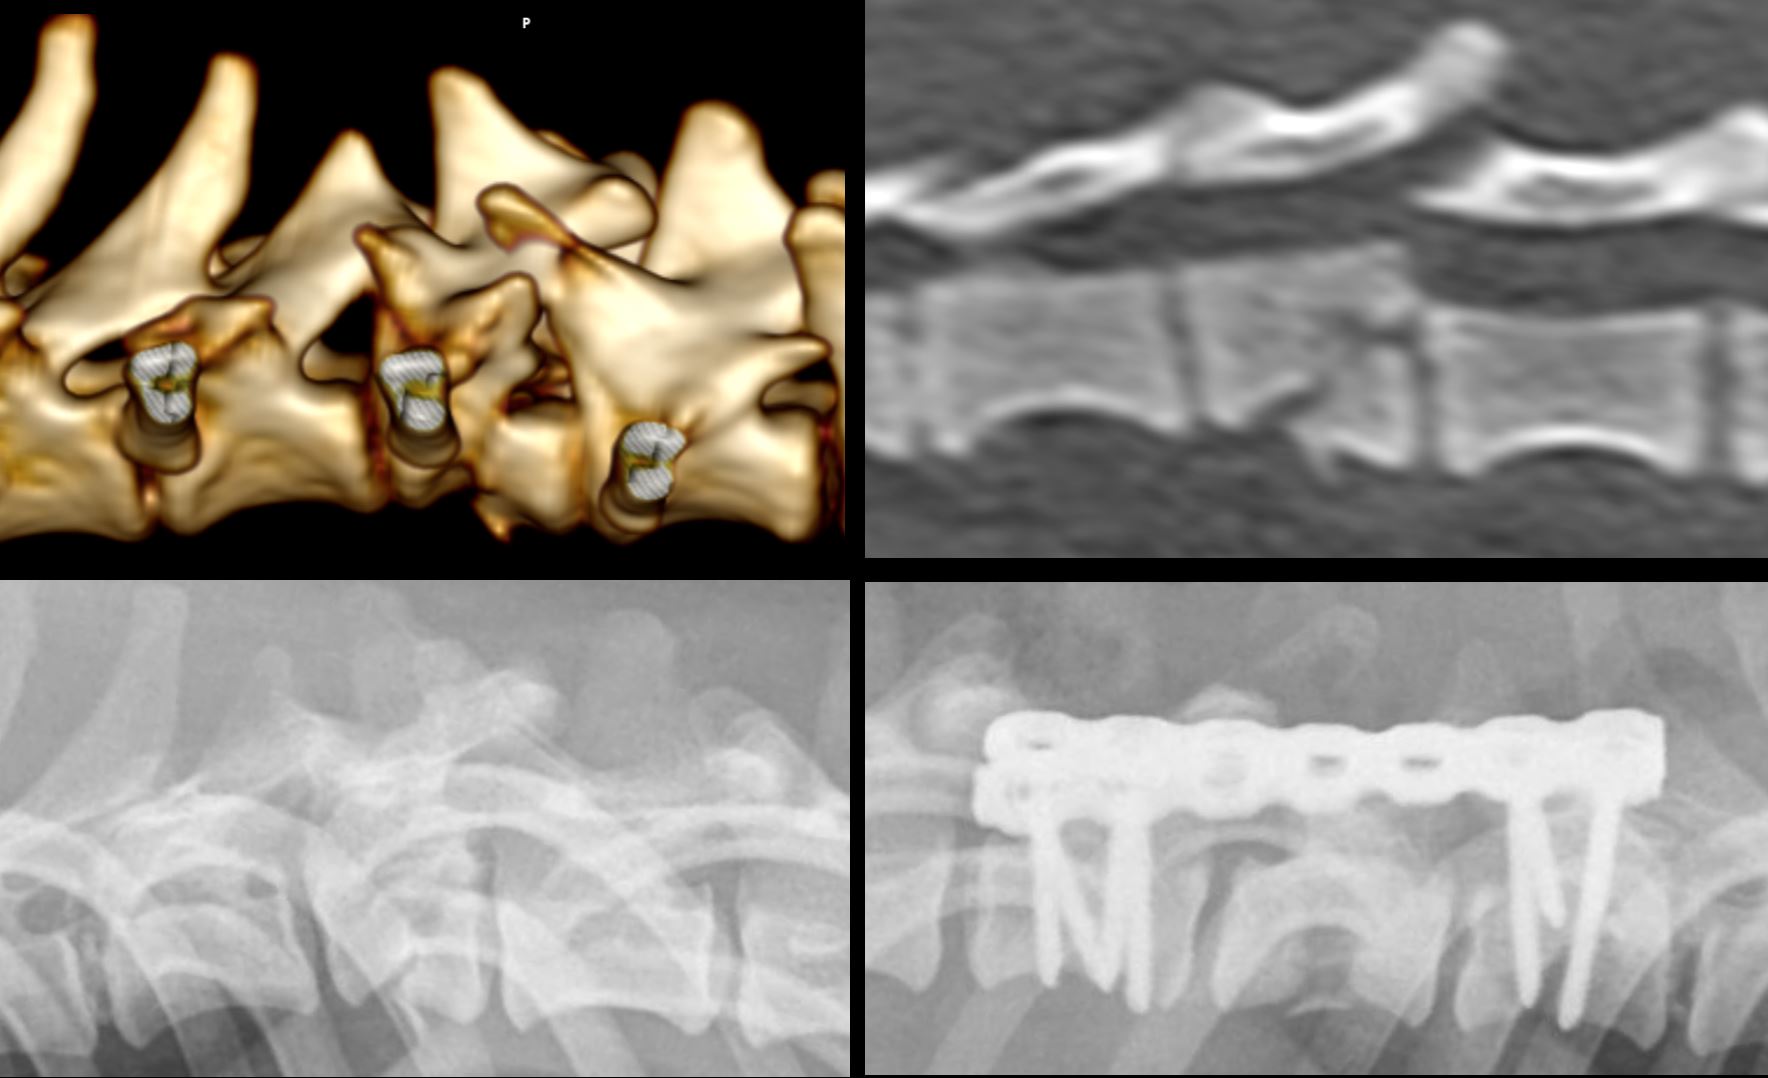

Começa a ser uma tradição a cirurgia de coluna de última hora!

Sou um felizardo porque tenho a melhor equipa do mundo!

Obrigado equipa Bonematrix!

Feliz ano novo a todos.... para o ano há mais!!!